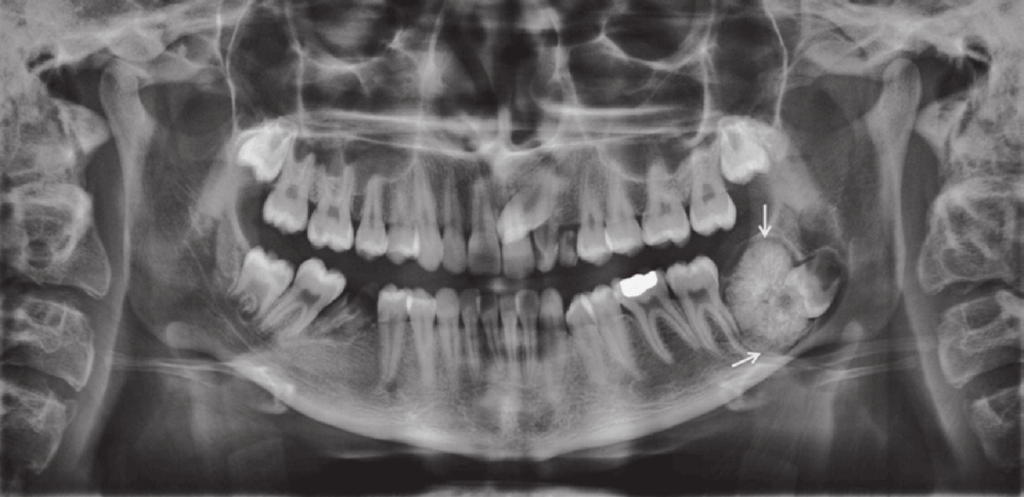

A 22-year-old man attended for treatment. He had a history of Gardnerʼs syndrome and noticed a bony hard lump on the ascending ramus of the mandible.

Gardner’s syndrome can also cause abnormalities in the jaw, including multiple osteomas, odontomas, and areas of hazy sclerosis. These dental findings may be one of the earliest signs of the condition and can help with early diagnosis.